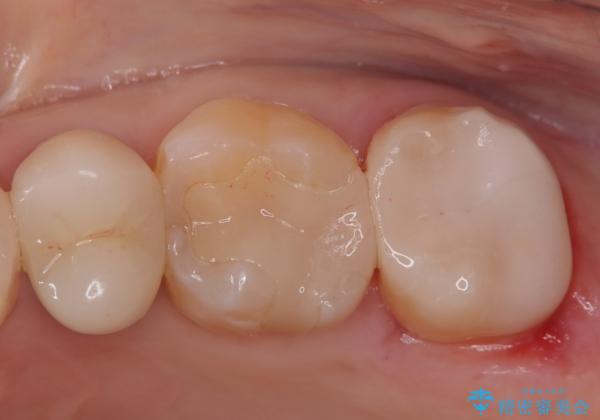

- 定期検診にて虫歯が見つかった患者様です。

金属のインレーの下と、歯と歯の間も虫歯だったため、つなげた形でセラミックインレーにて修復を行なっています。

e-max プレスインレーを用いることで、適合の良い治療ができます。